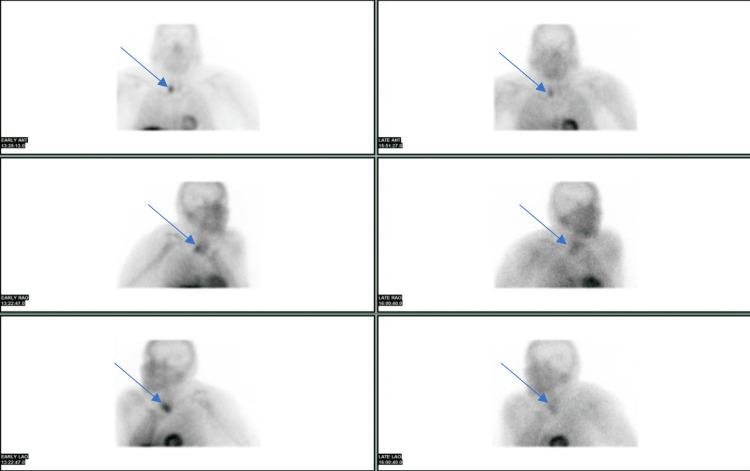

Parathyroid adenomas rarely weigh more than 4 grams. Our patient had a 5.3-gram adenoma causing bilateral knee pain limiting mobility, constipation, low back pain, and frontal headache. Presenting with calcium of greater than 17 mg/dl, the patient was treated with two rounds of hemodialysis, calcitonin, Zoledronate, and aggressive IV hydration to decrease calcium levels before parathyroidectomy. The patient then went on to develop the hungry bone syndrome, which was treated with calcium carbonate and calcitriol. This rare giant parathyroid adenoma presents a unique opportunity to learn about the pathogenesis and treatment of longstanding hyperparathyroidism causing hypercalcemia-associated symptoms and hungry bone syndrome after parathyroidectomy.

甲状旁腺腺瘤很少超过4克重。我们的患者有一个5.3克的腺瘤,导致双侧膝关节疼痛,限制了活动能力,还有便秘、腰痛和前额头痛。患者血钙高于17mg/dl,在甲状旁腺切除术前接受了两轮血液透析、降钙素、唑来膦酸治疗,并积极进行静脉补液以降低血钙水平。该患者随后出现了饥饿骨综合征,接受了碳酸钙和骨化三醇治疗。这种罕见的巨大甲状旁腺腺瘤为了解长期甲状旁腺功能亢进导致高钙血症相关症状以及甲状旁腺切除术后饥饿骨综合征的发病机制和治疗提供了独特的机会。